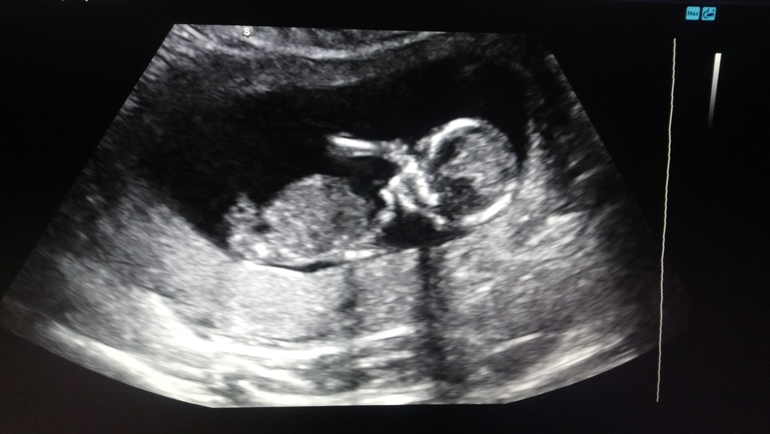

Я тоже переживала, т. к. была уже вб.

В больнице все пугали, что снова вб и то, что замер уже там, тьфу на них.

Сейчас мы уже такие))))